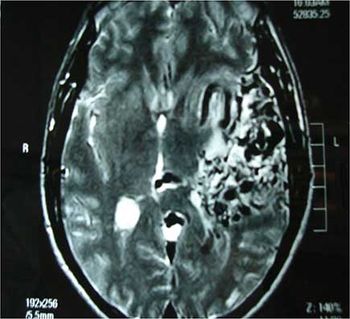

Case History: A 28-year-old man presented with history of pulsing noise in the head and progressive right hemiparesis.